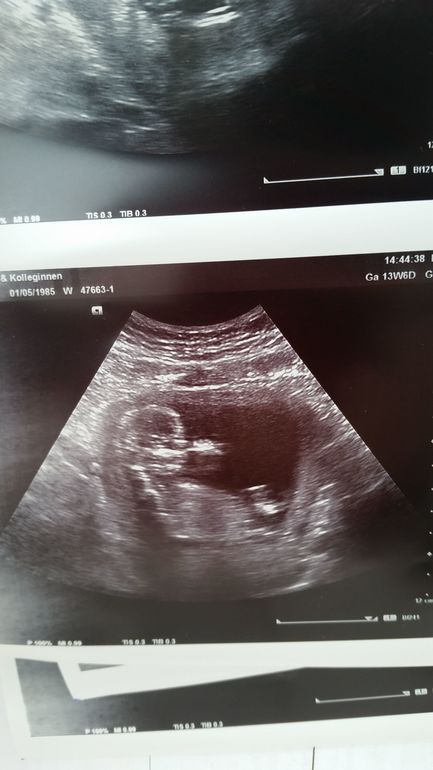

узи

Посещение и назначения врачей (стоматологи, кардиологи и проч.)сегодня нам 14 недель ровно и мы сходили к врачу на узи;) младшие дочь и сын были тоже на приеме и получили массу приятных ощущений, как и я

вобщем все соответствует сроку, сидит во мне попрыгунчик, все время прыгал и пальци на правой ручке насасывал;) мы уже 7 см. вобщем растет здоровый ребеночек. правда пол нам не сказали;( говорят еще не видно, но что то подсказывает что мальчик будет, хотя доча хочет сестренку, что бы было 2×2;)